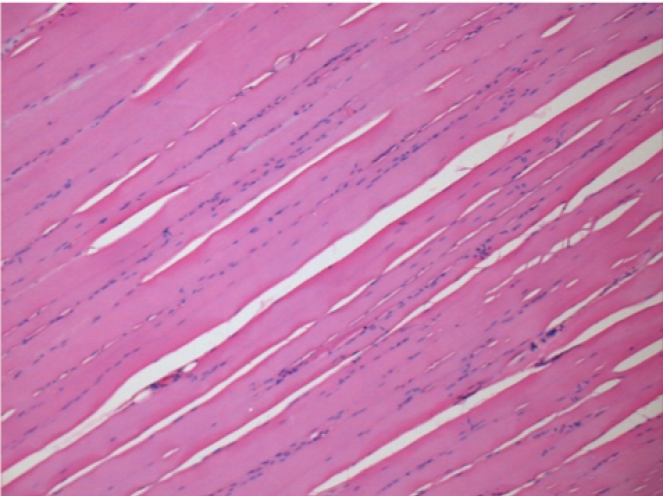

Controllo

Dopo iniezione di NaCl 0.5%

Commento : Niente da dichiarare dopo iniezione di soluzione fisiologica salina.

Sx:Pretibiale-Non trattato

Dx:Pretibiale-Dopo 0.1 ml NaCl 0.9% IM